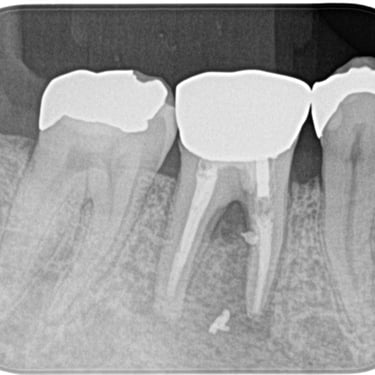

Calcificación Pulpar

La calcificación pulpar es la formación de depósitos de calcio dentro de la pulpa dental, que puede dificultar el tratamiento de conducto.

Los pacientes generalmente no tienen síntomas, pero pueden experimentar sensibilidad.

El tratamiento incluye la eliminación de los depósitos durante el tratamiento de conducto. Es importante tratarlo para evitar complicaciones durante el procedimiento.